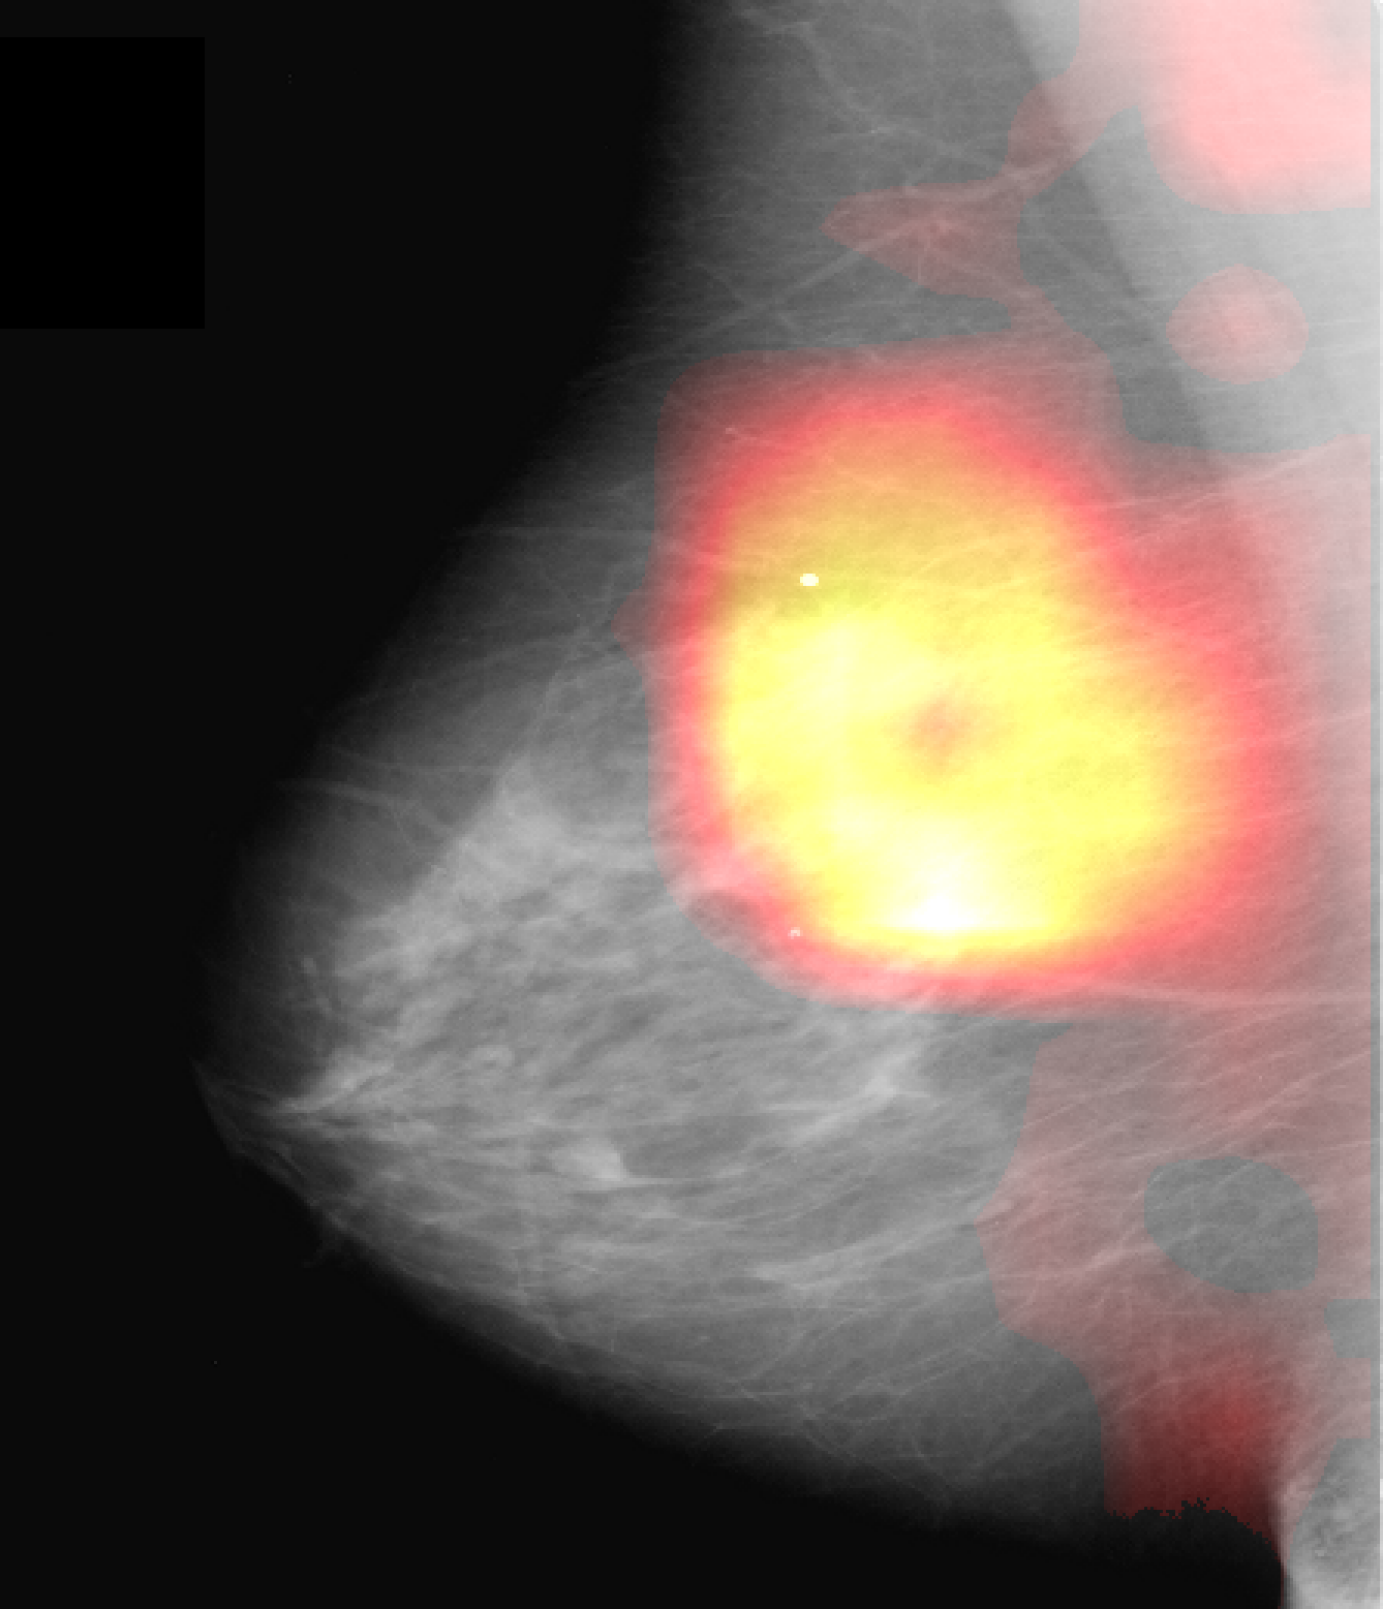

Saliency Evaluation: Quantitatively, our framework yields saliency masks significantly closer to GT masks based on Euclidean distances and Hausdorff distances , both substantiated by p-values below for all tested percentiles (cf. Table 1). Considering the map sizes (Table 2), we report overall significantly smaller masks, and again p-values below for all percentiles. This behavior changes when the shape-specific regularization parameters are relaxed, as exemplified by the ablation study. As shown in the last row of both parts of Table 1, our feature attributions become scattered and noisy. Close inspection of the overlap-values, esp. in Table 2, reveals that on average our method’s attributions have a higher overlap with SAL than CAM. This indicates that our results tend to adhere to the dense localization spots of SAL, but alleviate the latter’s noise and interpretation issue described in [3, 2].

Qualitatively, as depicted in Fig. 3 (b), our salient regions appear at the circumference of masses which is reasonable w.r.t. the fact that this is the discriminative region for the presence of masses. This is in line with [16], which reports on injection of poorly circumscribed, malignant looking masses while transforming healthy cases into pathological ones using a GAN variant. In addition, our method yields more accurate visualizations than CAM and SAL (Fig. 3 first row), i.e. it has a smaller, more precise and more informative feature attribution than these standard visualization methods (Fig. 3 (b)-(d)).